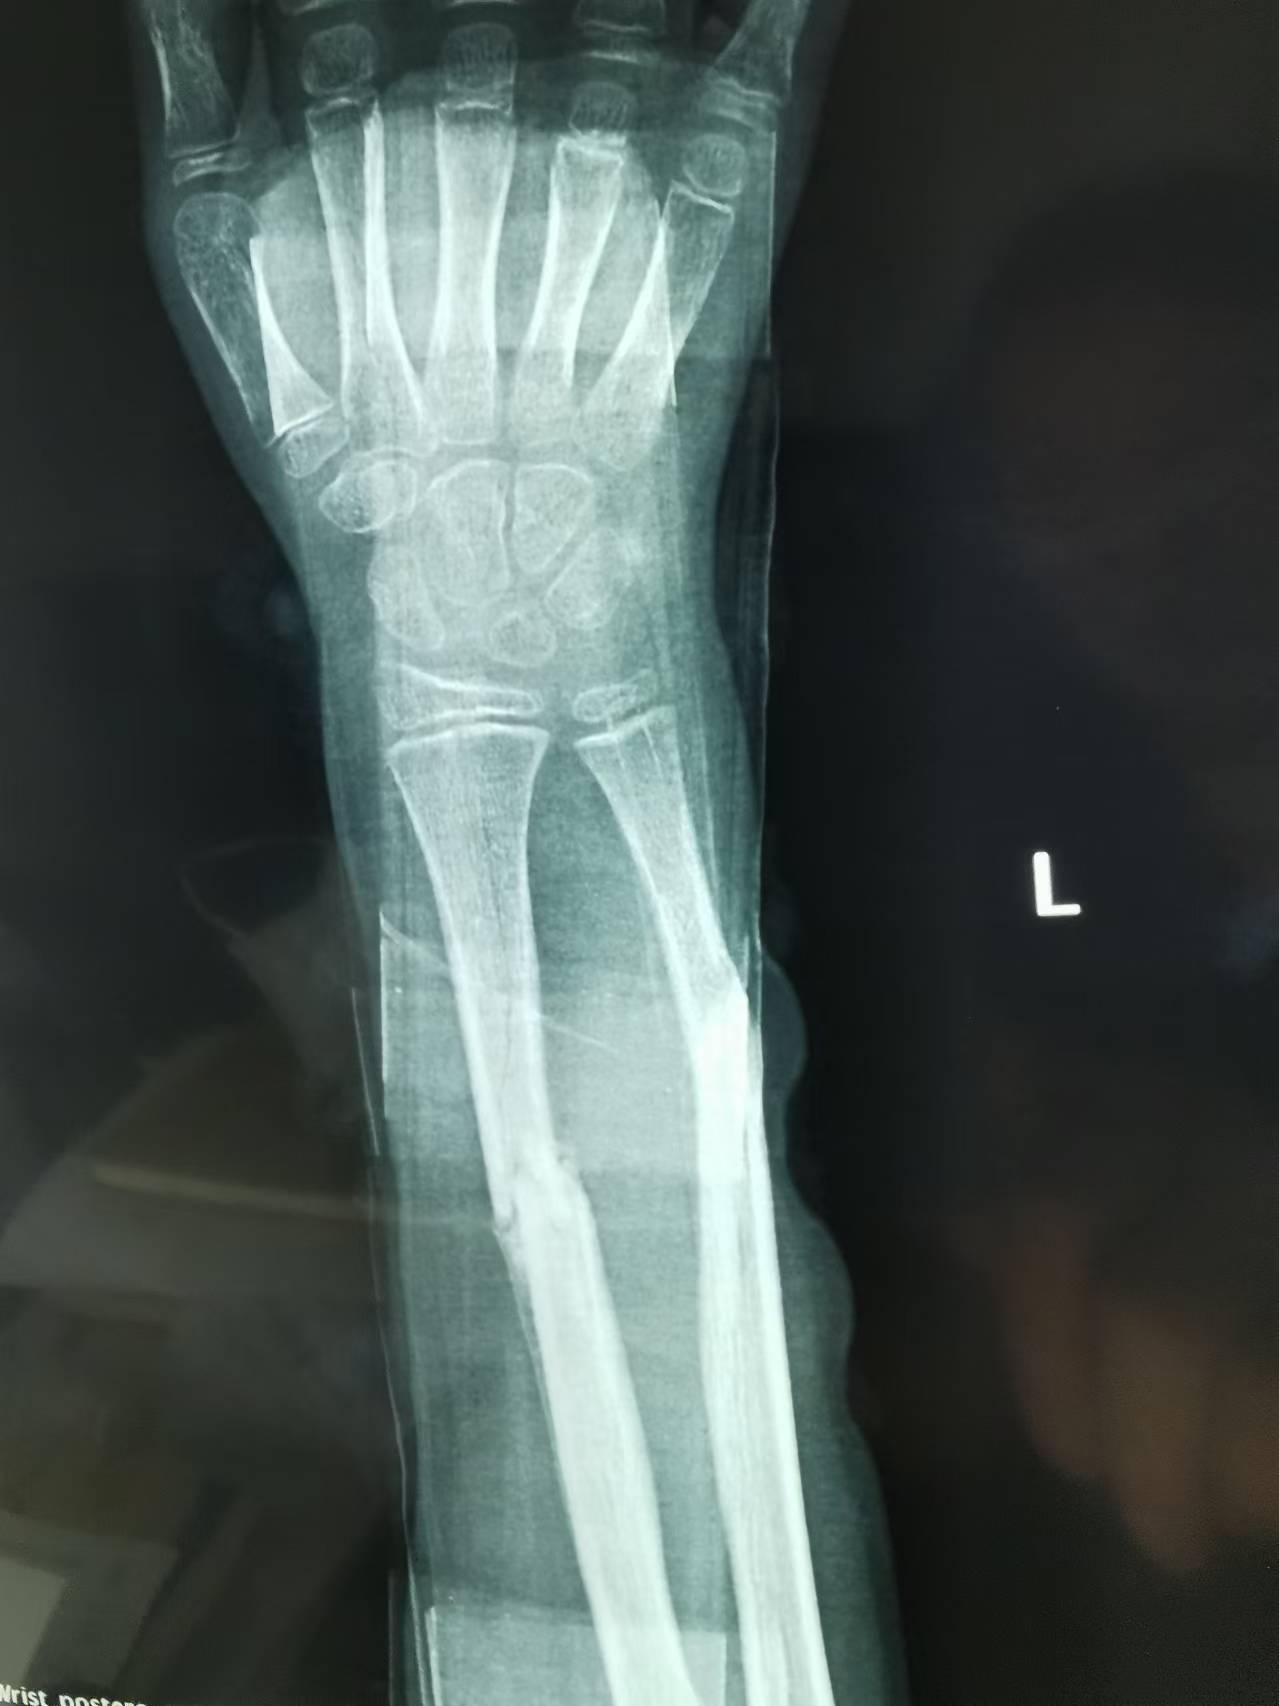

首页 > 张恒云工作室 > 影像资料 三